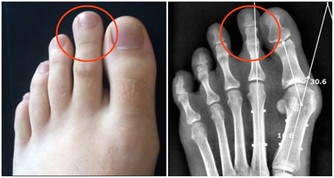

引起阻塞的原因乃是身體的毒素,亦即是有害人體的物質,如尿酸之類。

身體中的毒素,也可說是(污染物),多半是人體在吸收食品後,

它們往往停留在血管、肌肉、筋骨、關節以及臟腑的空隙中。